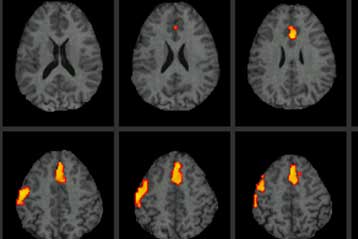

Ο εγκέφαλος των παχύσαρκων ανθρώπων είναι πρόωρα γερασμένος και σημαντικά μικρότερος σε σχέση με τα άτομα κανονικού βάρους, υποδεικνύει η πρώτη σύγκριση του είδους. Η παχυσαρκία συνδέεται με «σοβαρή εκφύλιση του εγκεφάλου» υποστηρίζουν οι ερευνητές.